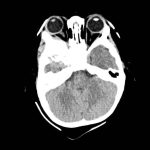

Fig. 2 Ecografia della lesione A-scan (ecogramma che mostra struttura a bassa reflettività, irregolare con angolo K negativo).